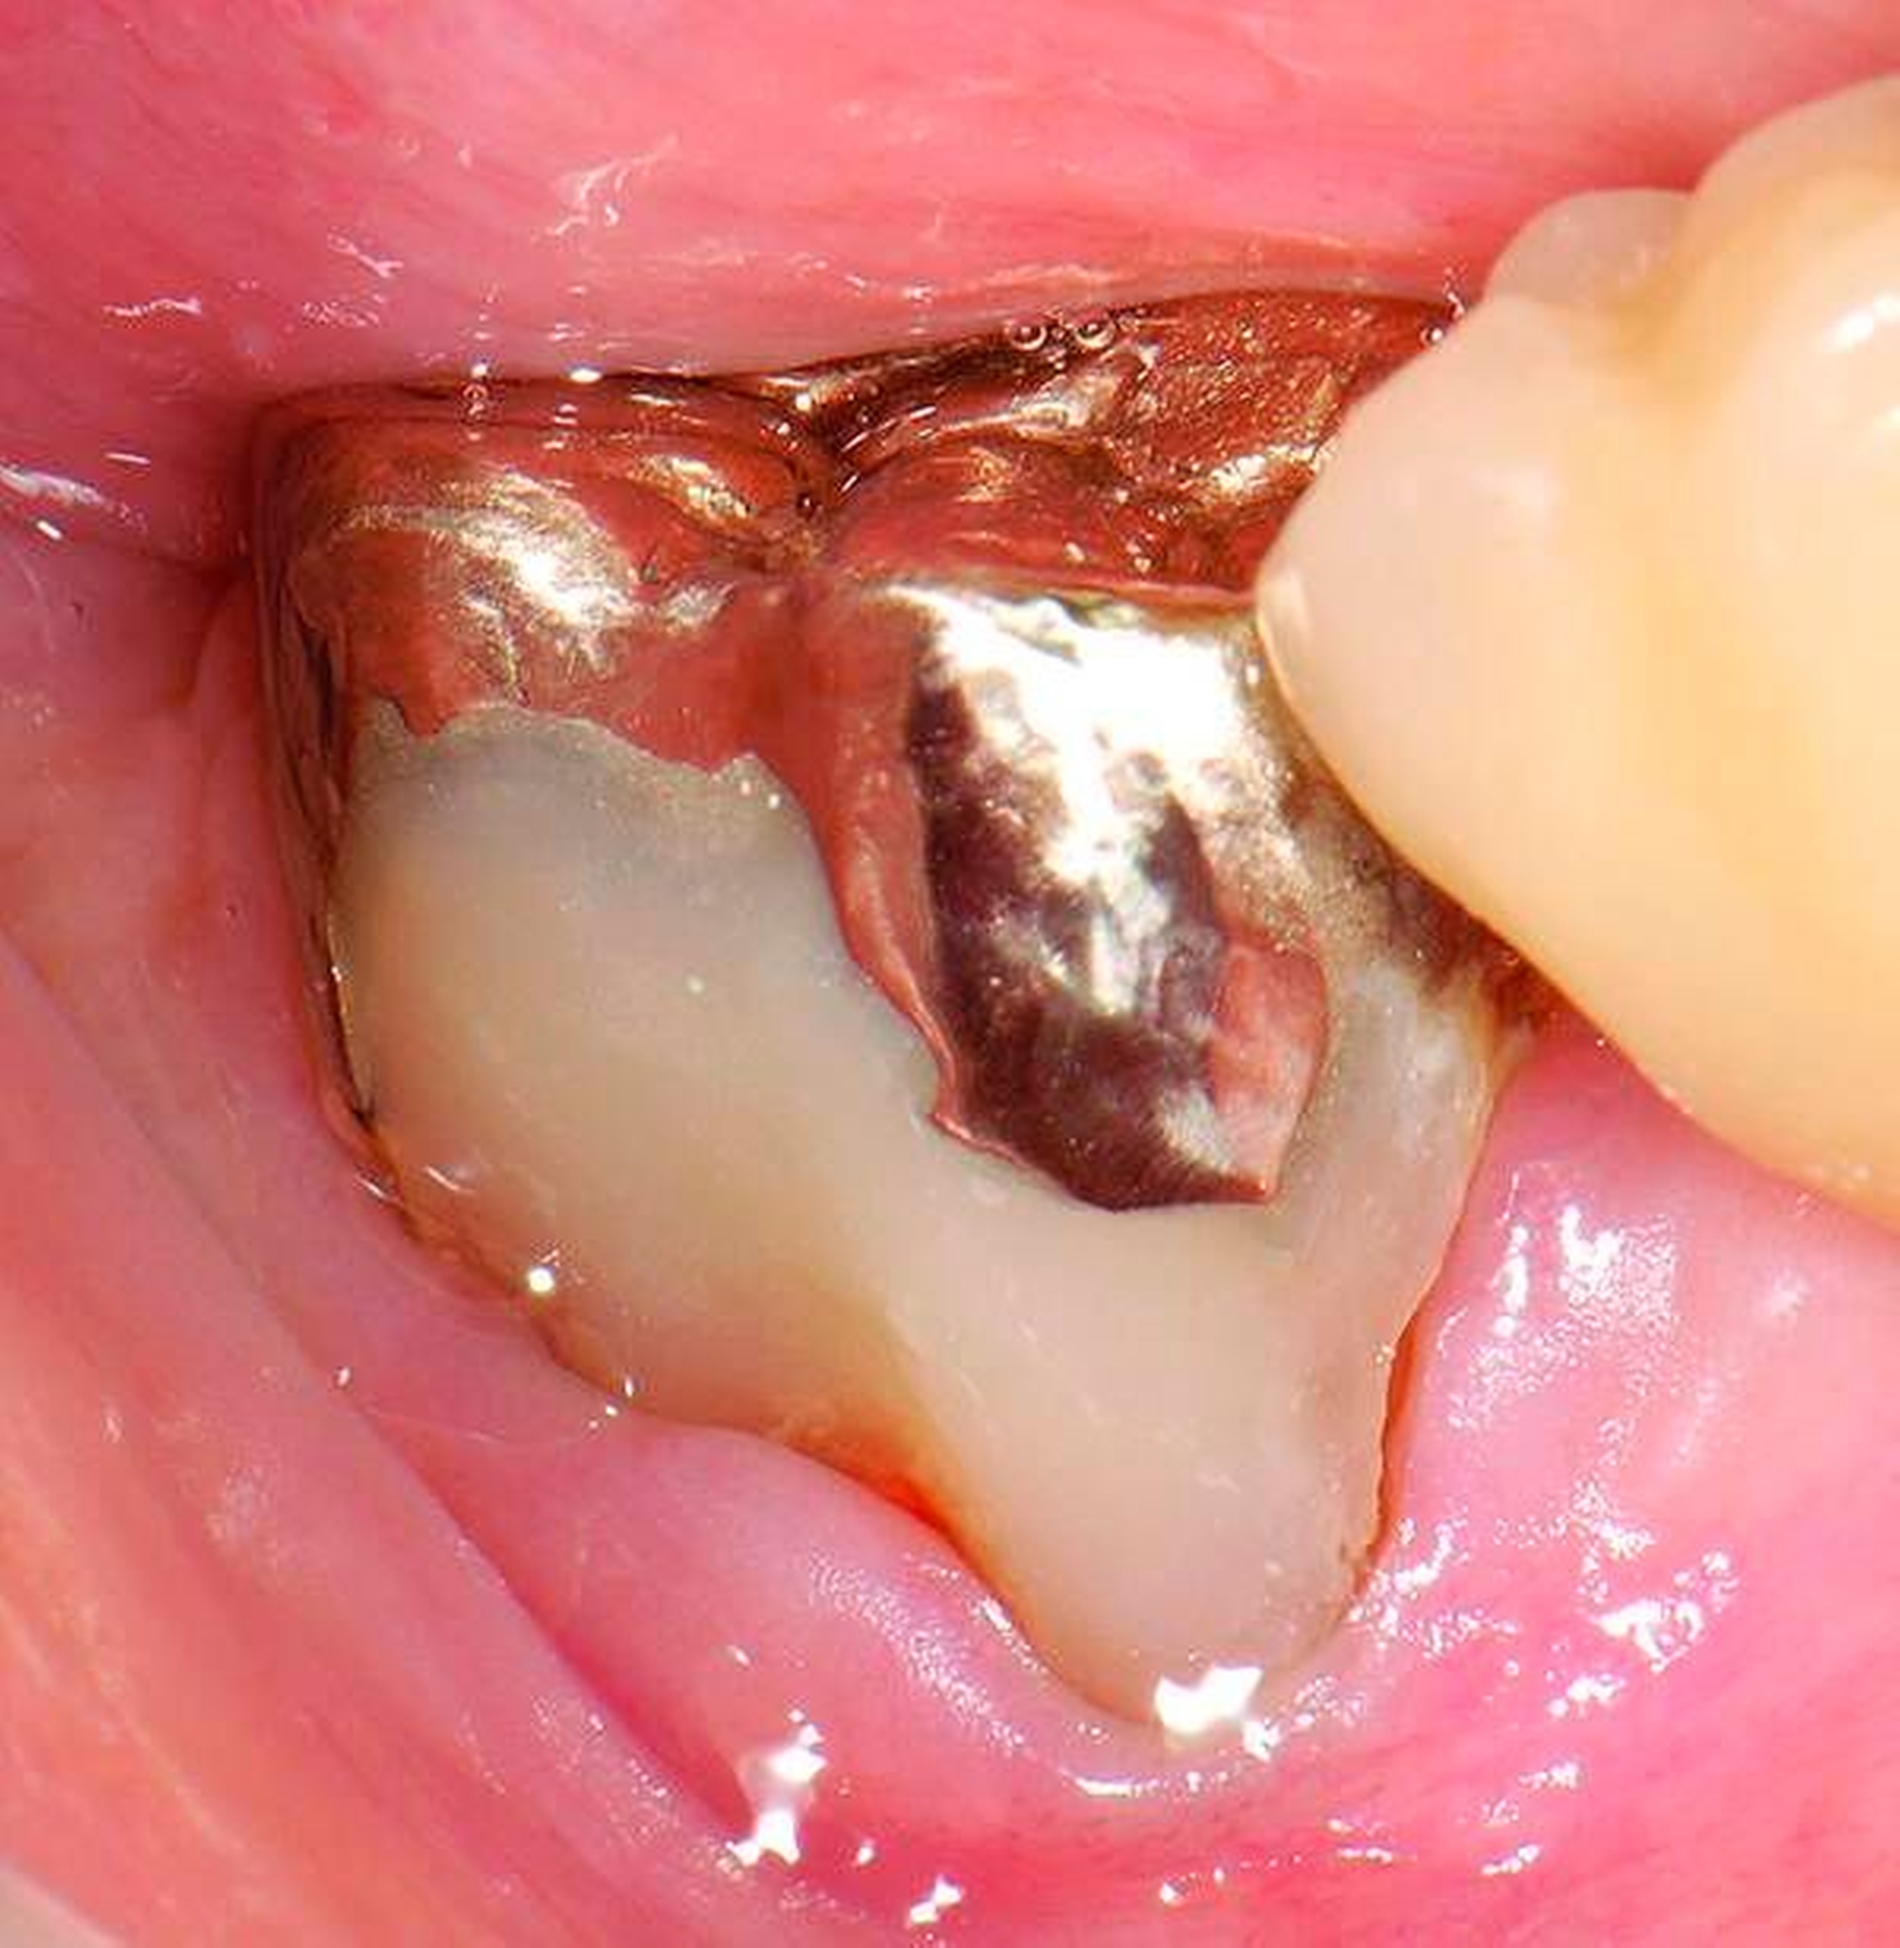

Abbildung 3: ausgedehnte Kronen- und Wurzelkaries unter einer Krone am Pfeilerzahn 47 einer seit Jahrzehnten eingegliederten Brücke von 45–47 bei einer 71-jährigen Patientin, die nach einer zerebrovaskulären Erkrankung unter Antikoagulantientherapie steht, vor etwa zwei Jahren hat sie eine Umstellung auf eine fluoridfreie Zahnpaste vorgenommen.

3. Restaurative Versorgungen bei Wurzelkaries

Freiliegende Wurzeloberflächen können im Alter ein locus minoris resistentiae für Karies sein. Im Zusammenspiel ungünstiger Ernährungsgewohnheiten, nachlassender Mundhygiene sowie Änderungen von Speichelquantität und -qualität kommt es zuweilen zu einem präventiv und restaurativ schwer beherrschbaren Auftreten von Wurzelkaries. Gut zugängliche Kariesläsionen können mit einphasig eingebrachtem Komposit (R1-Restaurationen) angegangen werden (Abbildungen 3 bis 5). Bei schwerer zugänglichen Arealen kommt ein zweiphasiges Vorgehen in Betracht (R2-Restaurationen). Das Vorgehen bei der R1- und bei der R2-Technik wurde mehrfach beschrieben [Frese et al., 2014a, b, c, d; Staehle et al., 2014, 2017]. Im Fall von zirkulärer Wurzelkaries sollte frühzeitig eingegriffen werden, da ansonsten die gesamte Zahnkrone frakturieren kann.